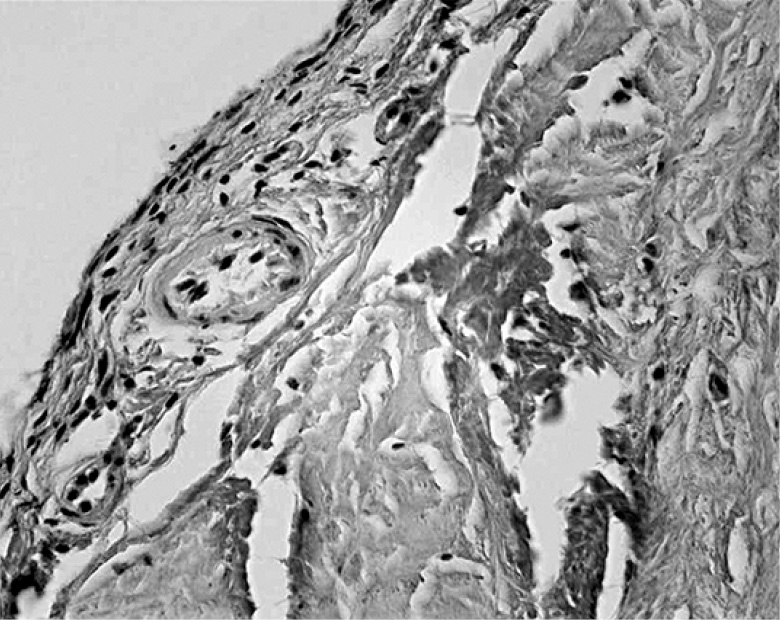

При гистоморфологическом исследовании было выявлено, что стенка кисты Бейкера устроена аналогично икроножно-полуперепончатой бурсе, при этом имелись признаки склероза, а в ряде случаев – слабовыраженная лимфоцитарная инфильтрация (рис. 1, 2). В строении стенки кисты чётко выделялись 2 слоя:

- внутренний – синовиальный (представленный синовиальными клетками),

- наружный – фиброзный слой (представленный плотной неоформленной соединительной тканью).

Рис. 1. Срез стенки кисты Бейкера (Г–Э, ×100). А – атрофичный синовиальный слой. B – фиброзный слой.

Fig. 1. A section of the wall of the Baker cyst (G-E, ×100). A – atrophic synovial layer. B – fibrous layer.

Клеточный состав стенки кисты был представлен фиброцитами, макрофагами, однокапельными адипоцитами и лимфоцитами. В обоих слоях выявлены единичные кровеносные сосуды (в основном капилляры). Электронограммы демонстрировали исчерченные коллагеновые волокна в обоих слоях стенки кисты. Клетки фиброцитов/фибробластов располагались между многочисленными жировыми клетками, имели слаборазвитые органеллы, многочисленные отростки (рис. 3).